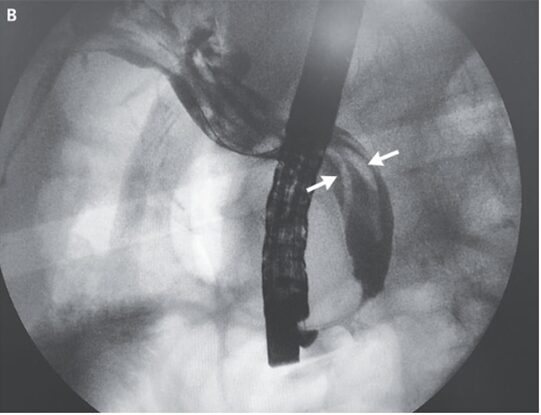

ERCP施行。胆管膨大部から虫が突き出ているのが観察された。摘出した結果、この虫は正中の回虫であることが確認された。

その後胆管造影が施行され、他にも2体存在することが示唆された(白抜けしている像)。

バルーンカテーテルを使用し、除去。